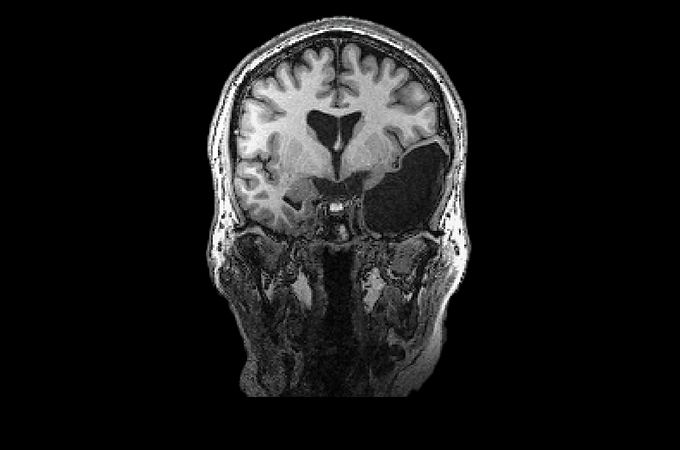

Elyse G. found out she lacked most of her left temporal lobe when she was 25 years old. The brain region is typically crucial for speech and language — but until her brain was scanned (three views shown), no one knew Elyse was missing hers.

Looking at her brain scans is a different story. It’s as if someone has knocked over a bottle of ink. The darkness pools inside her skull near her left ear, a puddle of fuliginous black. Inside the splotch, there’s no white matter or gray matter, no blood vessels or tissue at all.

Elyse says you don’t have to be a neurosurgeon to spot what’s different about her brain: “There’s a big honking piece missing!”